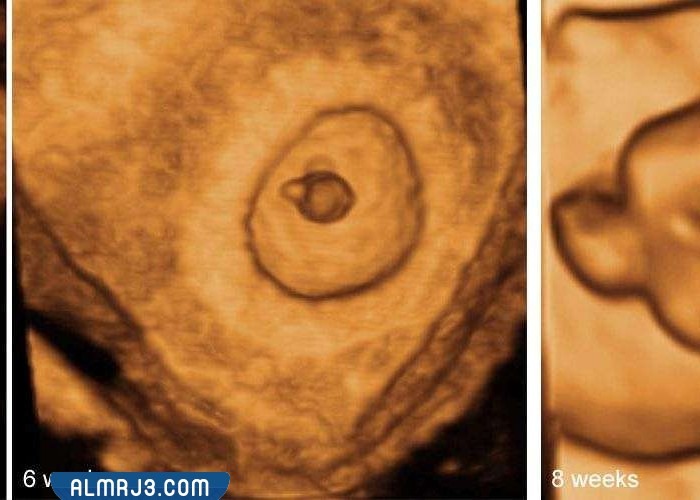

شكل كيس الجنين الذكر في الشهر الثاني

يمكن أن يختلف شكل كيس الجنين سواء أكان ذكرًا أو أنثى في الشهر الثاني من جنين لآخر حسب الطبيعية الجسدية للأم وطبيعة الجنين الذي سيتكون حيث يمكن أن يتخذ كيس الجنين الشكل الدائري أو البيضاوي، أما بالنسبة لحجم كيس الجنين في الشهر الثاني فغالبًا ما يكون صغيرًا جدًا ولا يجاوز ال4 مليمترات أثناء الشهر الثاني من الحمل منذ بدايته وحتى نهايته.

لا يختلف كيس الجنين في الشهر الثالث عن كيس الجنين في الشهر الثاني سواء أكان الجنين ذكرًا أم أنثى إلا من حيث حجم الكيس حيث يزداد حجم كيس الجنين في الشهر الثالث من الحمل حتى يصل إلى 12 مليمترًا بنهاية الأسبوع الثاني عشر، وتكون الزيادة في حجم كيس الجنين أثناء الحمل في الشهر الثالث تدريجية حيث يزداد ليصل إلى 6 مليمترات أثناء الأسبوع التاسع من الحمل ثم إلى ثمانية مليمترات أثناء الأسبوع العاشر من الحمل وهكذا حتى يصل إلى حجمه النهائي في نهاية الشهر الثالث.